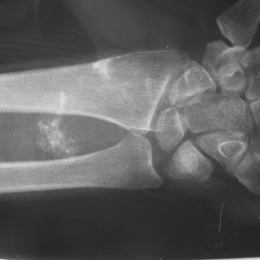

Synovial Sarcoma Of Wrist Area Wit Calcifications

• • The work-up often consists of a physical examination, X-rays, CT scans, MRI, and sometimes bone scans are required. CT scans can be used to check for subtle mineralization that may help with the diagnosis